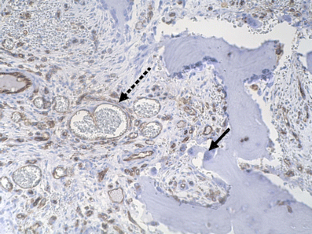

The histological examination revealed a mesenchymal tumor with numerous capillaries and dilated vessels immunohistochemically being positive for CD31, but not for D2-40. In addition, there was a remarkable increase of osteoclasts that sometimes exhibited Howship’s lacunae. The tumor was diagnosed as intraosseous hemangioma with prominent bone degradation.

Fig. 2